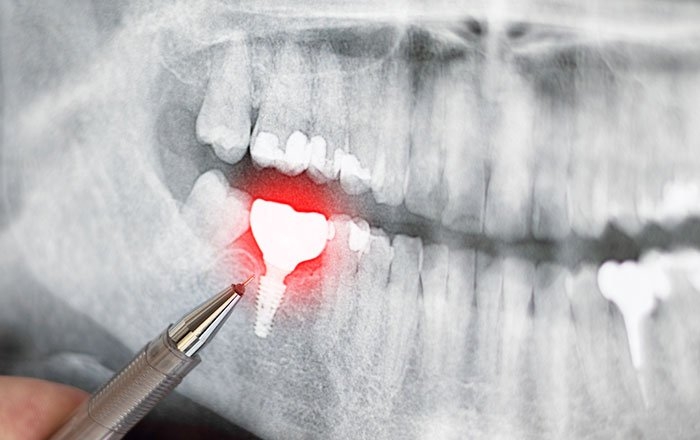

インプラントの手術後は、歯茎を切開した傷が残っており、周辺の組織に炎症が起きている状態です。

インプラント体(フィクスチャー)と骨の結合を妨げる可能性がある

インプラント体(フィクスチャー)が骨と結合するためには、その周囲が適切な温度を保っている必要があります。そして骨は約47〜50℃以上の熱が長時間加わると、骨細胞が変性するリスクがあるといわれています。

レーザー脱毛やハイフ(※)などの施術で発生する熱がインプラント体の金属に伝わると、周囲の骨にも余計な熱が加わってしまい、インプラントと骨の結合がうまくいかなくなる可能性が出てきます。